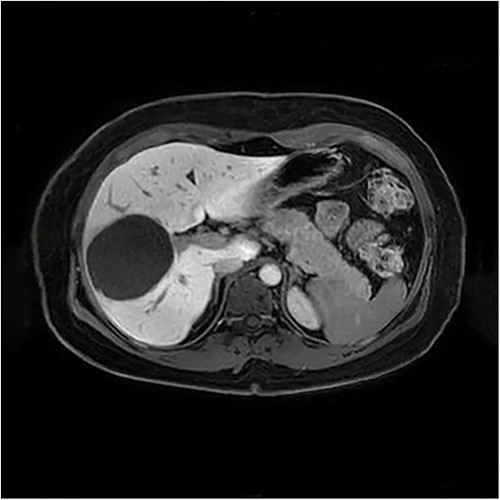

The presenting patient was a 40-year-old Brazilian native who had lived in Europe for ~26 years. Initially, the patient presented to her general practitioner with upper right quadrant pain. An ultrasound study (Fig. 1) showed a small hyperechoic lesion in segment VII measuring ~0.8 × 0.9 cm. Follow-up studies showed an expanding lesion with newer hyperechoic portions. In 2020 a liver specific magnetic resonance imaging (MRI) (Fig. 2) was performed. Here, again, the cyst was expanding, septated and had reached a size of 7.3 × 6 × 6.5 cm. A Echinococcus infection was considered, however, repetitive EIisa for Echinococcus sp./IgG was negative. The alpha protein was 2 ug/L, and well within normal limits. Due to increasing discomfort, an upper gastrointestinal tract endoscopy was performed. Here, gastritis and gastro-intestinal neoplasia could be excluded.